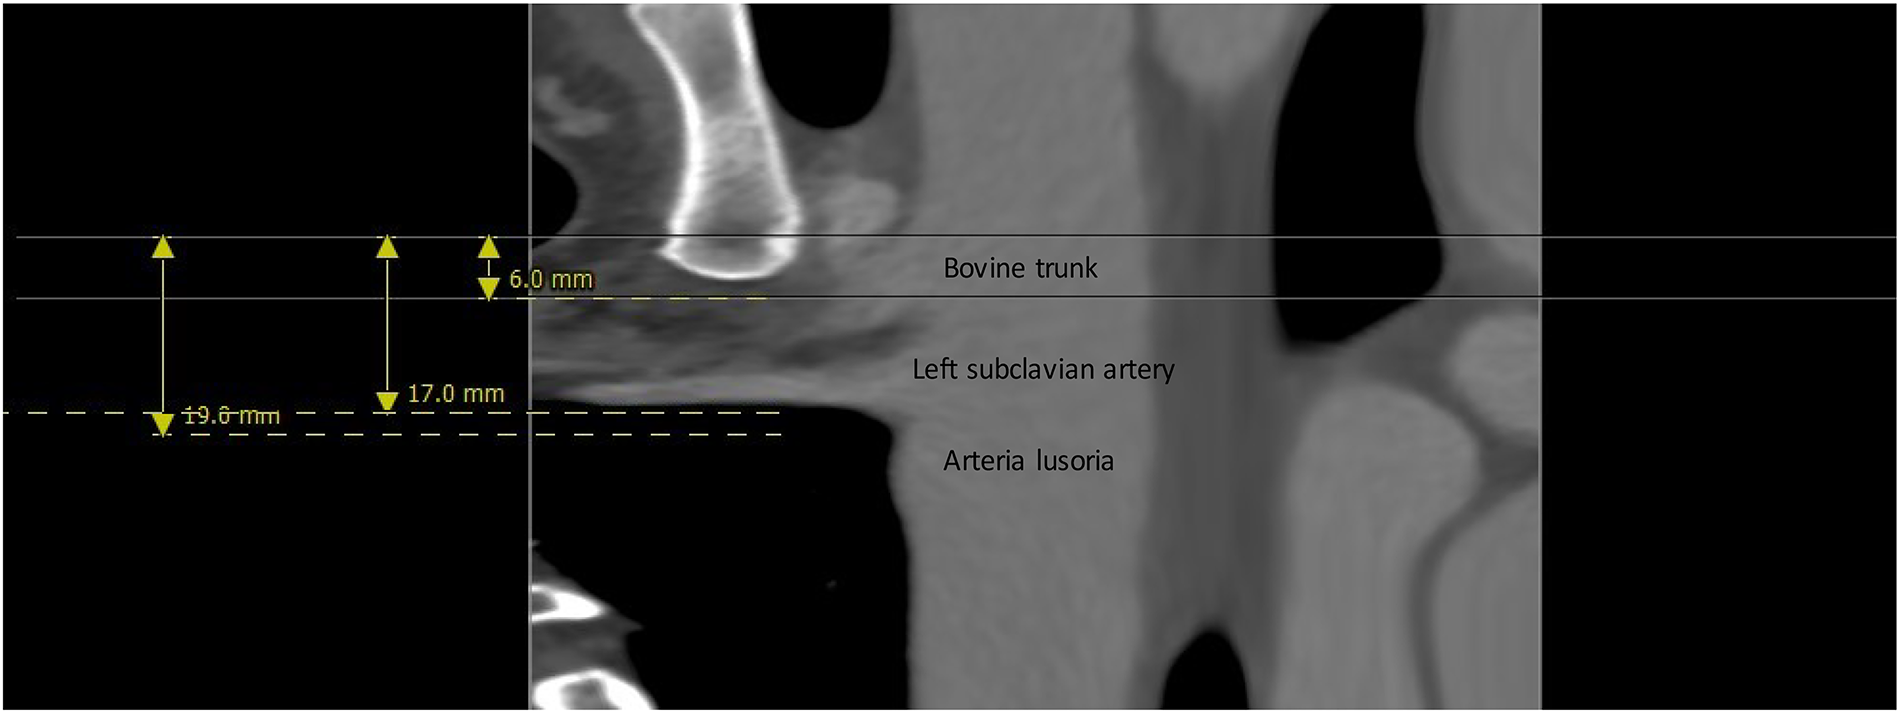

A 44-year-old patient underwent gastric bypass surgery in 2015, resulting in a remarkable weight loss of 30 kg. The patient presented with a progressively worsening dysphagia over the past six months. Diagnostic investigations revealed a pulsatile compression of the esophagus, suggestive of dysphagia lusoria. Subsequent computed tomography (CT) imaging confirmed the presence an aberrant origin of the right subclavian artery from the aortic arch which exhibits ectasia in its proximal portion (Kommerell diverticulum), with a diameter reaching up to 17,8 mm and a retroesophageal course causing compression on the posterior wall of the esophagus. Additionally, there is a presence of a bovine bicarotid trunk, with a 17 mm distance separating it from the subclavian artery. Centerline reconstruction emphasized a narrow 2 mm space between the arteria lusoria and the left subclavian artery (Figures 1, 2). Given the symptomatic nature of the condition and the concurrent presence of Kommerell's diverticulum, surgical intervention was deemed necessary. However, due to the close proximity of the bovine trunk and the arteria lusoria, treatment by TEVAR or hybrid open surgery was considered tedious and relatively at risk.

Figure 1. 3-Dimension reconstruction and sagittal CT scan view revealing an aberrant origin of the right subclavian artery from the aortic arch and a dilated appearance of its proximal segment (17.8 mm), with a retro-esophageal course.

Figure 2. Center line reconstruction imaging by 3mensio medical imaging (utrechtThe Netherlands): It underscores the remarkably proximity between the arteria lusoria and the bovine trunk, measuring a mere 13 mm, alongside the minimal 2 mm separation between the AL and the left subclavian artery.